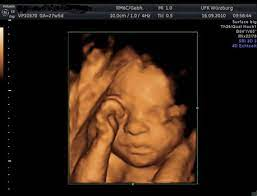

• Primera ecografía tridimensional

Primera ecografía tridimensional

se realiza la primera ecografía tridimensional en Austria con un aparato de la casa Kretz.